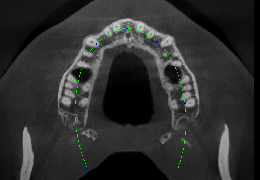

ANYTHINK 经导管主动脉瓣膜置换术分析系统